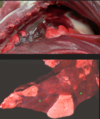

3

Q

This is the stomach of a horse. What lesion is shown here?

A

equine gastric ulceration